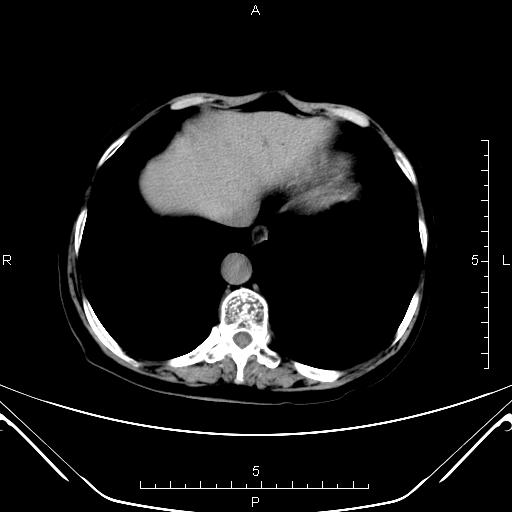

CT49600:中上腹CT

本帖最后由 ldm1993 于 2014-12-19 18:47 编辑 女,77岁,胆囊切除术后1个月,中上腹不适1周,胃镜示:十二指肠乳头上见一广基粘膜下隆起,乳头口粘膜绒毛状结节不平。 ...

两处病灶,从强化方式上看,考虑十二指肠乳头腺癌,伴胰头周围淋巴结转移可能。

考虑十二指肠乳头腺癌,伴胰头周围淋巴结转移可能。

腹腔感染,脓肿形成。

支持壶腹癌